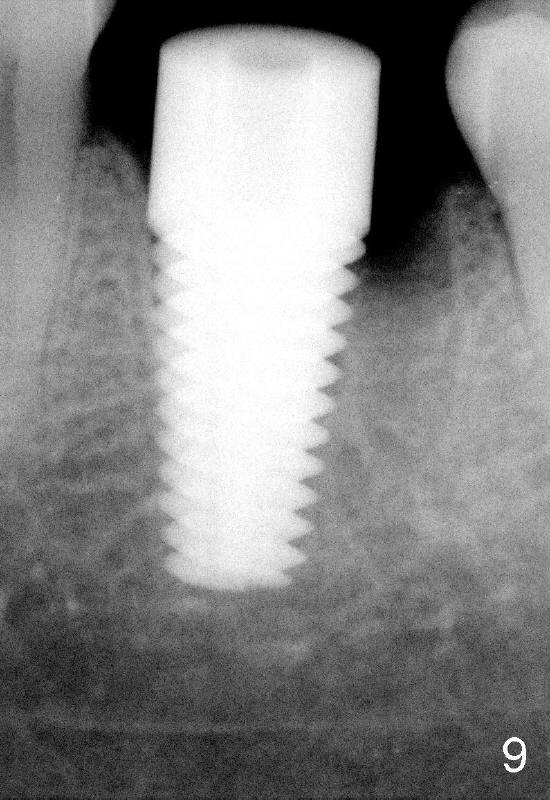

When 7x17 mm tap is placed, it drops mainly into the mesial socket (Fig.8). The septum appears to have been pushed to the distal one (<). When the 7x17 mm implant is placed with primary stability, the top portion is in the middle of the edentulous space (Fig.9). Sutures are placed mesial and distal to close the socket (Fig.10). The wound heals normally 3 months postop (Fig.11: ^). There is no bone resorption; the bone density on the top of the distal socket increases (Fig.12: D). The crown is fabricated 1 month later.